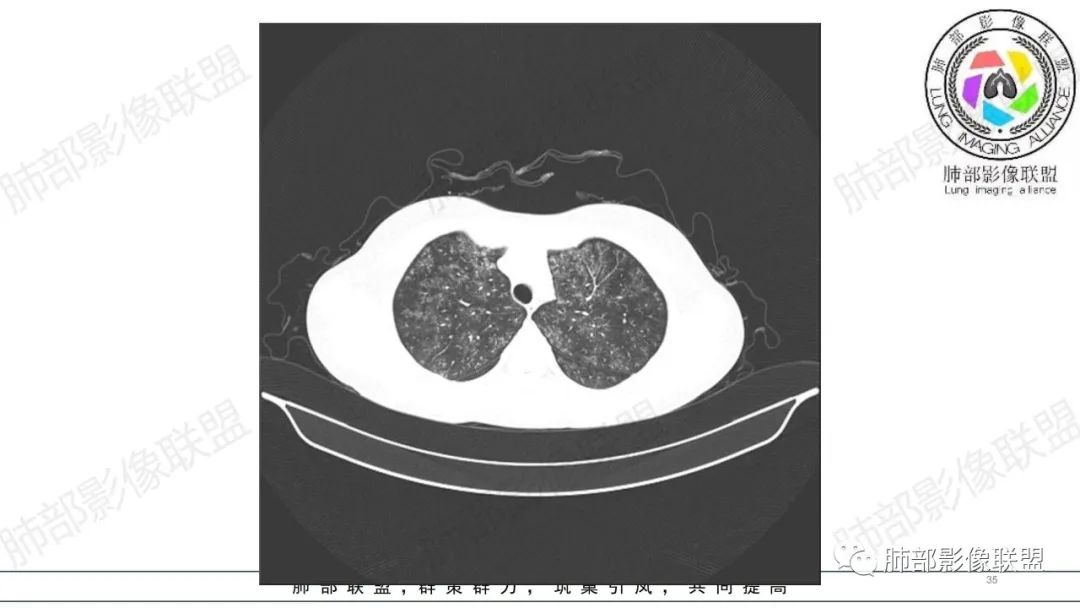

34岁女性患者,“哮喘”病史30年,近期有可疑刺激性气体吸入史;因乏力半年,咳嗽、憋气、发热4天就诊;6.1CT提示双肺广泛毛玻璃影及粟粒样结节,胸膜下闲置及血管周闲置,可见树丫征,部分小叶间隔增厚。考虑:1.过敏性肺泡炎,有可疑刺激气体接触史,胸膜下闲置,广泛毛玻璃影,地图样分布,粟粒结节边界模糊,支持过敏性肺泡炎,但糖皮激素治疗效果不佳,且动态复查血常规血红蛋白进行性降低,过敏性肺泡炎 不符合;2.肺含铁血黄素沉积症:患者30“哮喘”病史,可能为肺含铁症状,肺部CT提示双肺弥漫毛玻璃影及粟粒结节影,中下肺明显,肺底部分小叶间隔增厚,近期咳嗽、憋气、发热,血常规血红蛋白进行性下降,考虑肺含铁急性期症状,但临床无咯血症状,肺含铁不典型。综合考虑:肺含铁血黄素沉积症>过敏性肺泡炎。

年轻女性 ,急性喘息发热,肺部影像弥漫磨玻璃密度,部分细小腺泡结节,胸膜下黑线显示,短期复查,病变密度增高,下肺明显,血管周围肺组织累及较少、且逐渐成小叶间隔分布。考虑弥漫肺泡内病变,并经淋巴道转移,下肺比上肺明显,多为免疫细胞功能下肺较强。1.过敏性肺泡炎,有相关病史,三层密度特点、头尾测分布,符合。2 肺泡微石症,多有钙化,且缓慢起病,病程不太符合,放待排。3 吸入相关肺损伤,有病史,疾病演变过程也符合渗出-肉芽肿改变,建议详细询问病史。4 感染性病变,结核?病变气道分布为主,如此弥漫且没有树丫不符合。5.巨细胞病毒,可以磨玻璃 结节 改变,没有免疫缺陷病史。最后考虑吸入所致 1过敏性肺泡炎、吸入性肺损伤 鉴别肺泡微石症。

肺内气腔磨玻璃结节,肝脾肿大,治疗后间质改变,弥漫大B可能